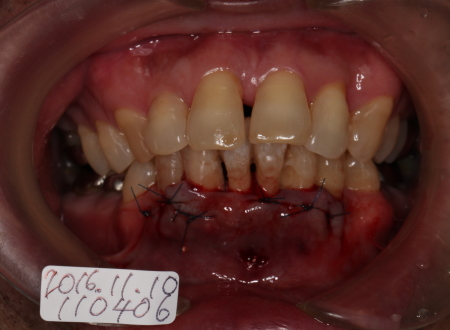

2016-11-11

FOPの翌日

痛みもほとんどなく歯ぐきの状態も良好